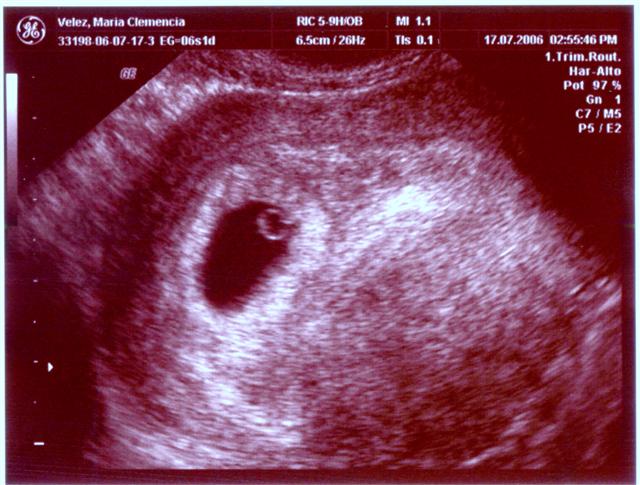

Categoria Desde la barriguita

Hola! Por aquà todo muy bien, Creciendo rápidamente. Mi mamita se ha sentido muy bien en general. De vez en cuando le da un poquito de cansancio y ultimamente un poquito de mareos. Todo es normal en esta etapa. Mi papito la mima y la consiente. Claro, entre mas caricias mas mareos. Si ven la relación? A mi mamita lo que le gusta es que mi papito la mime y la consienta 🙂